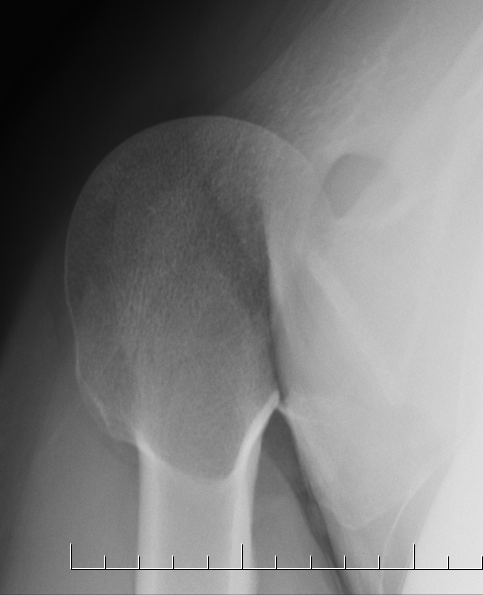

Isolated lesser tuberosity avulsion

Lesser tuberosity avulsions in adolescents / skeletally immature

Traumatic avulsion of the lesser tuberosity and subscapularis insertion

- frequently missed on xray

- delayed presentation

Previous history of trauma

Anterior shoulder pain

Subscapularis weakness

Lesser tuberosity can become overgrown